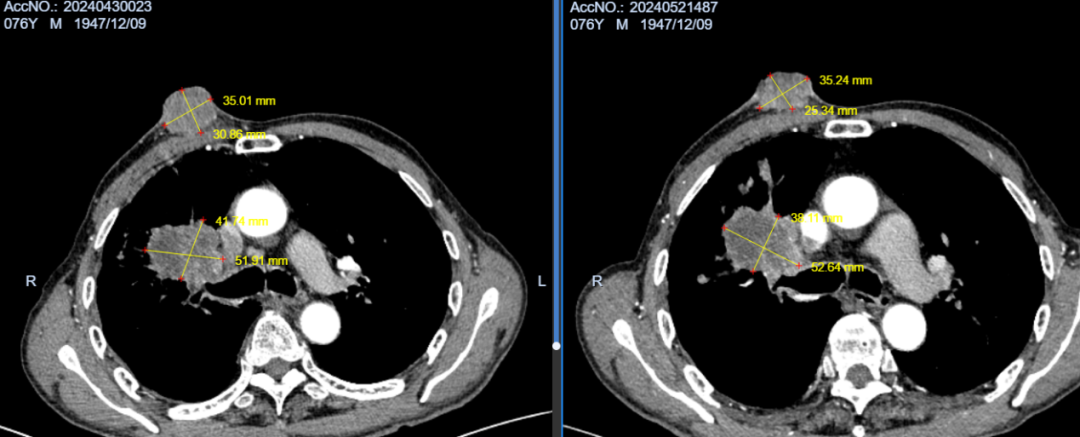

术前CTA                              术后1月余

术后2月余,胸壁继发恶性肿瘤基本坏死,肺内原发病灶缩小明显,坏死空洞形成。